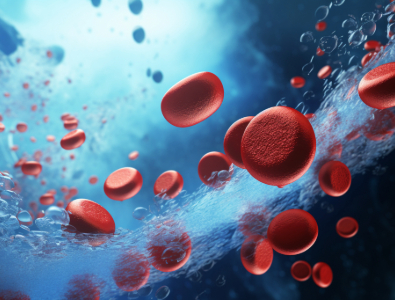

Die hyperbare Sauerstofftherapie (HBOT) ist eine weltweit anerkannte, nicht-invasive Behandlung, die durch klinische Forschung gestützt wird. Sie wird unter erhöhtem Druck verabreicht und verbessert die Sauerstoffdurchlässigkeit und -konzentration im Körper, wodurch die Selbstheilung gefördert wird. HBOT ist eine sichere Methode zur Förderung der Stammzellenzirkulation. Die präventive Sauerstofftherapie unterstützt das Immunsystem, beugt Sauerstoffmangel vor und schützt das Gehirn. Die Behandlungen sollten bei chronischen Erkrankungen systematisch durchgeführt werden, wobei die empfohlenen Dosierungen einzuhalten sind. Hyperbarkammerbehandlungen sind für alle Altersgruppen geeignet und fördern Gesundheit, Fitness und Anti-Aging.

Regeneration der Stammzellen

Revitalisierung und Stimulierung ruhender Zellen

Wir haben uns für hochwertige medizinische Geräte entschieden, weil nur sie die Möglichkeit bieten, die Behandlungsparameter genau auf die spezifischen Bedürfnisse jedes Patienten abzustimmen und höchste Sicherheit gewährleisten. Eine entscheidende Komponente der hyperbaren Sauerstofftherapie ist der Überdruck, bei dem die Therapie durchgeführt wird. Studien und klinische Erfahrungen zeigen, dass ein Druck von mindestens 2 ATM notwendig ist, um den Sauerstofftransport im Körper signifikant zu erhöhen und die therapeutische Wirkung zu maximieren. Dieser Druck ermöglicht es, den Sauerstoffgehalt im Blutplasma drastisch zu steigern, was die Heilung von Geweben fördert und die Wirksamkeit der Therapie deutlich verbessert.

Die Behandlung findet in einer Überdruckkammer statt und wird individuell auf den Patienten abgestimmt. Um eine maximale therapeutische Wirkung zu erzielen, erfolgt die hyperbare Sauerstofftherapie in einem Überdruck von mindestens 2 ATM. Dieser spezifische Druck ist entscheidend, um den Sauerstoffgehalt im Blutplasma signifikant zu erhöhen, wodurch die Heilung von Geweben gefördert und die Wirksamkeit der Therapie maximiert wird.